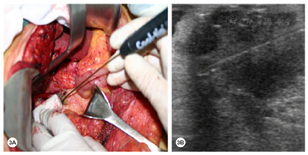

结合胸部CT和胃镜,可初步排除胃癌复发和转移。综合影像学报告和辅助检查,初步诊断为胰腺癌、胆囊结石和胆囊炎。术中超声显示肿瘤大小为4.0 cm×3.5 cm,包绕并侵犯肝总动脉根部;肿瘤经穿刺活检证实为低分化PDAC(图2)。

患者来本院寻求手术治疗,遂决定行开腹手术。开腹探查发现胰颈部可见一质硬实性肿块,向胰腺上缘突出。结合术中情况,患者无胃癌复发迹象,肿瘤与肝总动脉、肝固有动脉及胃十二指肠动脉关系密切,考虑难以行手术切除,因此决定行术中超声引导下RFA治疗。Kocher钳游离胰头和十二指肠。患者曾接受过根治性胃切除术,因此游离胰腺上缘的膜性粘连。分离肝十二指肠韧带右缘,冷湿纱布覆盖周围组织器官,充分暴露胰头和胰颈。采用Cool-tip™ RFA系统以及冷循环电极(17-gauge)(图3A)。然后在术中超声引导下将射频电极精确地插入肿瘤内(图3B)。启动后设置手动功率输出,从40 W开始,随后将功率以10 W/min速率增加,以90 W的最大功率进行肿瘤消融,共消融3点次(每次6~10 min)。于胰体及winslow孔置管引流(图4)。术后予以抗感染,抑酸,抑制胰腺分泌对症支持治疗。